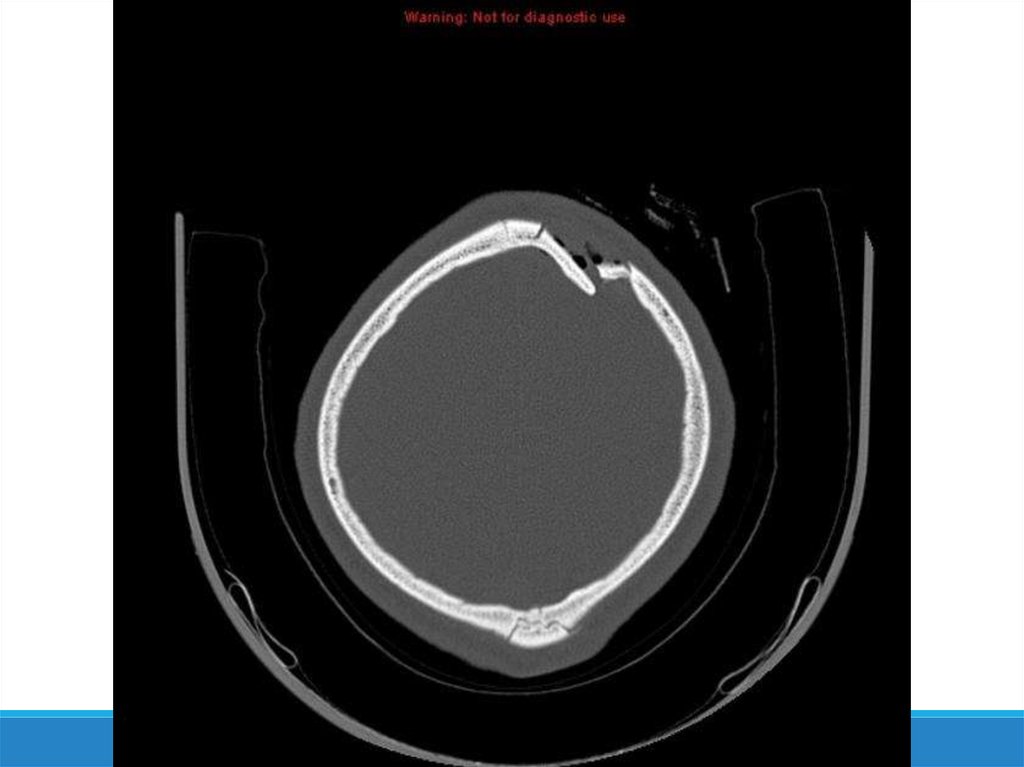

-Компьютерная томография